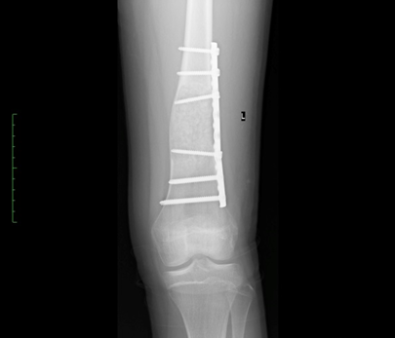

Post-operative xray of a distal aneurysmal bone

cyst treated with curettage, grafting and plating.